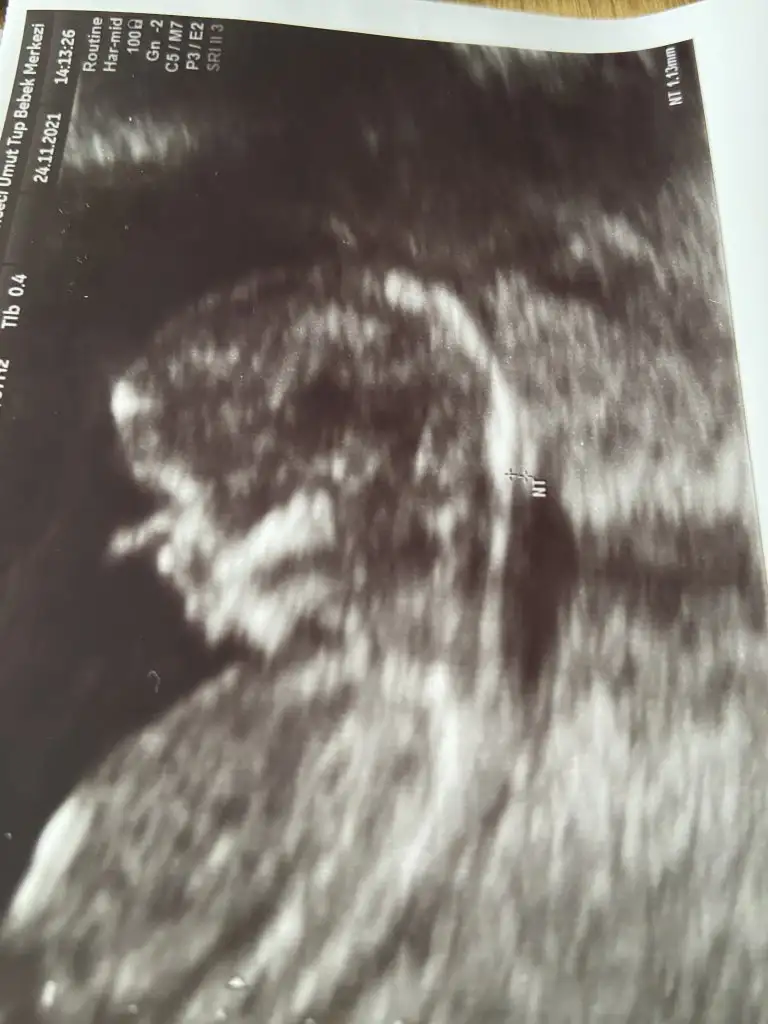

ahanda bir yerinde durmayan kuduruk bebek daha. zıp zıptı benimki de :) dans ediyor gibiydi. doktor sana cinsiyet için ne demişti kuzuBugün gittim doktora ense kalınlığı falan gayet güzel dedi. Ama ben şok bebek bildiğin kuduruyordu. Ayaklarıyla ittirip zıplıyordu muayene boyunca. Doktor zor baktı. Aşırı hareketli dediDedim kuduruk olacak

Yaaa maşallah, günün ikinci zıp zıpı.Bugün gittim doktora ense kalınlığı falan gayet güzel dedi. Ama ben şok bebek bildiğin kuduruyordu. Ayaklarıyla ittirip zıplıyordu muayene boyunca. Doktor zor baktı. Aşırı hareketli dediDedim kuduruk olacak

Abooovvvv hemde nee kudurukkk görüyonmu zıplıyorr bideBugün gittim doktora ense kalınlığı falan gayet güzel dedi. Ama ben şok bebek bildiğin kuduruyordu. Ayaklarıyla ittirip zıplıyordu muayene boyunca. Doktor zor baktı. Aşırı hareketli dediDedim kuduruk olacak

fotolarda görüldüğü üzere parmak emenler kulübünden, aç kaldı yavrucak